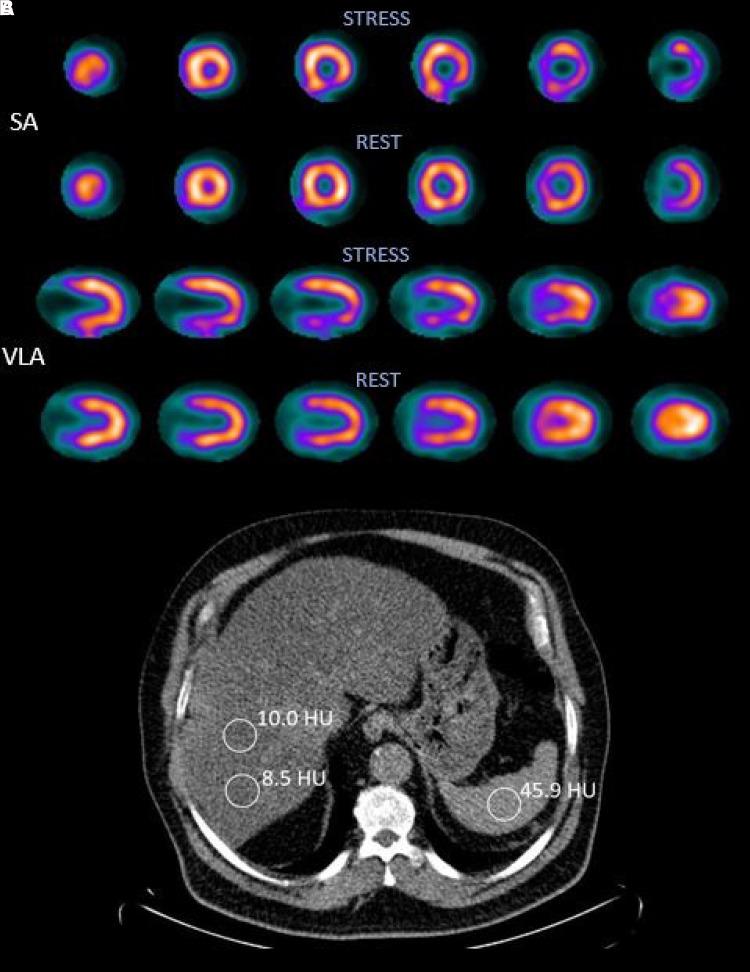

We analysed 742 patients who had undergone MPI using single photon emission computed tomography (SPECT) and LDCT. A liver-to-spleen ratio (in Hounsfield units) of <1 was defined as FLD. Myocardial ischaemia was defined as a summed difference score (SDS) ≥3. Left ventricular size and systolic function were assessed from the electrocardiogram-gated SPECT. FLD patients were younger (63 vs. 68 years) and had a higher body mass index (34.6 vs. 29.0 kg/m) and a higher SDS (2.65 vs. 1.63), < 0.001 for all. Independently of several possible confounding factors including traditional risk factors, patients with FLD had a 1.70-fold risk of ischaemia (95% confidence interval 1.11-2.58, = 0.014). Left ventricular end-diastolic volume (109 vs. 109 mL) and ejection fraction (61 vs. 61%) were comparable in those with and without FLD (non-significant for both).

我们分析了742例行单光子发射计算机断层扫描(SPECT)和LDCT的MPI患者。肝脏与脾脏的比值(以亨氏单位计)<1被定义为FLD。心肌缺血被定义为总差异评分(SDS)≥3。从心电图门控SPECT评估左心室大小和收缩功能。FLD患者更年轻(63岁对68岁),体重指数更高(34.6对29.0 kg/m),SDS更高(2.65对1.63),所有差异均<0.001。独立于包括传统危险因素在内的几个可能的混杂因素,FLD患者发生缺血的风险高1.70倍(95%置信区间1.11 - 2.58, = 0.014)。有和没有FLD的患者左心室舒张末期容积(109对109 mL)和射血分数(61对61%)相当(两者均无统计学意义)。